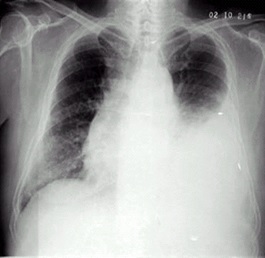

02卷-4.男性,24歲,發(fā)熱、咳嗽、咳痰4天。診斷(本題滿分2.00分)

A.右上肺不張

B.右上胸膜肥厚

C.右上肺癌

D.右上肺炎

本題答案:D

題目解析:【該題針對(duì)“X線-肺炎”知識(shí)點(diǎn)進(jìn)行考核】